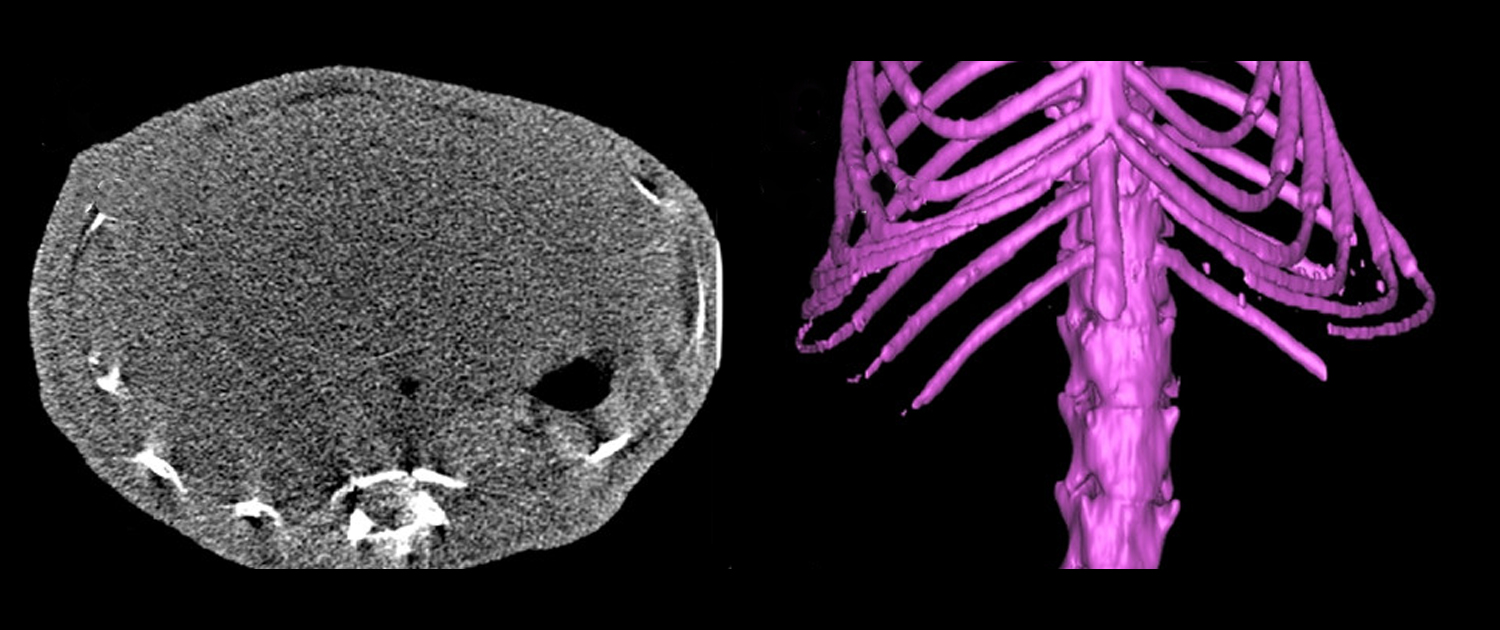

Micro-Computed Tomography (micro-CT) is a non-invasive imaging technology that is widely used in both preclinical and clinical research. In preclinical research, micro-CT is employed to visualize internal anatomy and assess bone density, tissue composition, and microarchitecture, and monitor disease progression in animal models. It is also used to evaluate the efficacy of therapeutic interventions and assess the safety of new medical devices and drugs. Micro CT scans provide high-resolution, three-dimensional images of internal anatomy, which can reveal intricate details about the biological structure of tissues and organs.

In clinical research, micro-CT is used to examine bones and joints, detect early signs of osteoporosis and assess the therapeutic response to treatments. It is also used in dental research to evaluate the mineral density and structure of teeth, and in cardiology to visualize the coronary arteries and assess the distribution of plaque in the arterial walls. The ability to visualize internal anatomy in such detail provides valuable information for researchers and clinicians, allowing them to make more informed decisions about patient care. Additionally, micro-CT is also useful in forensic medicine, allowing the examination of bones to determine the cause of injury or death.

Micro-CT in Preclinical Imaging

Organ Morphology Evaluation

Micro CT provides researchers with a non-invasive method for assessing organ morphology in small animal models. The 3D images generated by the system allow for a detailed evaluation of the structure and function of various organs, including the heart, liver, and lungs.

Micro-CT in Bone Studies

Bone Density Analysis

Micro CT can be used to assess bone density, which is a crucial parameter in evaluating bone strength and the risk of fractures. This application is important for the early diagnosis and treatment of osteoporosis and other bone disorders.

Bone Microarchitecture Assessment

Micro CT provides a detailed view of the bone’s internal structure, which allows researchers to evaluate the bone’s microarchitecture, such as trabecular thickness, spacing, and orientation. This information is essential for understanding the mechanical properties of bones and the effects of various treatments on bone health.